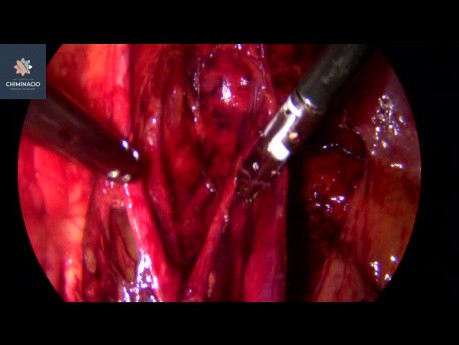

Infertilité - chirurgie de l'endométriose

La chirurgie d'endométriose en cas d'infertilité est bien acceptée comme un moyen qui augmente la probabilité d'une grossesse spontanée. Cette vidéo montre pas à pas une intervention chirurgicale qui...